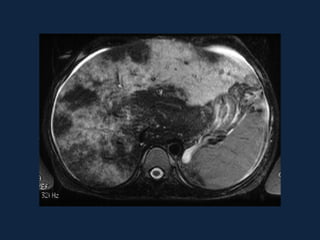

SÍNDROME DE BUDD-CHIARI

• Obstrução da drenagem venosa

hepática no plano das veias

hepáticas ou da VCI.

• Associada às síndromes

mieloproliferativas, trauma, HPN,

carcinoma hepatocelular, gravidez e

uso de anticoncepcionais.

• Ascite, hipertrofia do lobo caudado,

hipertensão portal, aspecto “em

mosaico” do parênquima hepático.

Distribuição perivascular

• Budd-Chiari

– Aumento do lobo

caudado

– Atrofia do restante do

parênquima

• “Compressão

periférica”

– Nódulos regenerativos

•  T1

• ,  ou  T2